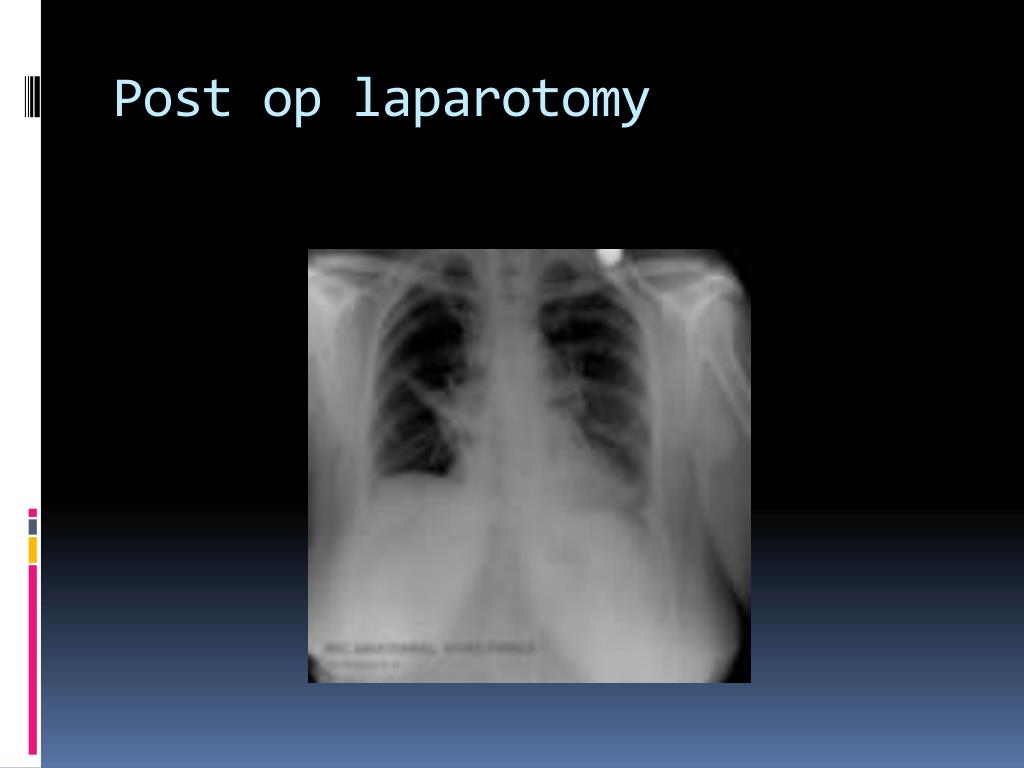

47. Post op laparotomy